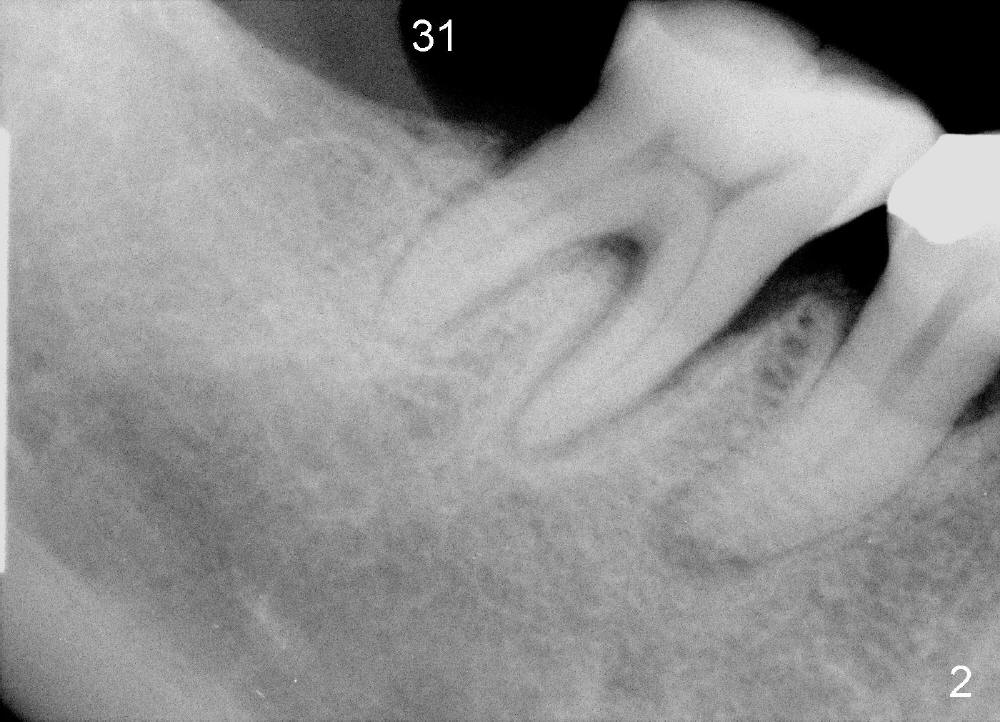

A 57-year-old lady returns for #31 implantation. The vertical edentulous space is limited, as the opposing tooth is supraerupted (Fig.1 arrow). Preop PA is critical (Fig.2), since it is used to measure the bone height (Fig.3: 12 mm). The length of the implant is expected to be 10 mm. The initial osteotomy depth is 8 mm (Fig.4); it appears that the trajectory should be adjusted. Osteotomy increases following depth and angulation adjustment (Fig.5: 4.5x10 mm drill). The submerged implant (5.3x10 mm) is placed with insertion torque approximately 35 Ncm (Fig.6). The buccal microthreads are exposed (Fig.7); to prepare for bone graft, the buccal plate is decorticated. Following placement of freeze dry mineralized allograft, collagen membrane is fixated by a healing screw (Fig.8). The incision is closed by 4-0 Chromic gut sutures and perio glue (Fig.9).

Bone-level implants offer two options after placement (stages 1 and 2). If the insertion torque is high and there is sufficient vertical edentulous space, a healing abutment is placed (stage 1). No surgery is required for restoration. Otherwise, the implant should be buried, as shown in this case. Two mini-implants are going to be placed to intrude the opposing supraerupted tooth. In fact, the orthodontic intrusion is quite difficult. Finally the intrusion apparatus has to be removed prior to chemotherapy for breast cancer. PAs taken 1 year 3 months (Fig.10) and 1 year 9 months (Fig.11, 6 months post cementation) postop appear to show that there is coronal bone loss. An abutment with short cuff (Fig.11 *) is chosen for final crown (C). Ideally the implant should have been placed deeper (Fig.7) for easy restoration. Pre-op examination and diagnosis are critical.